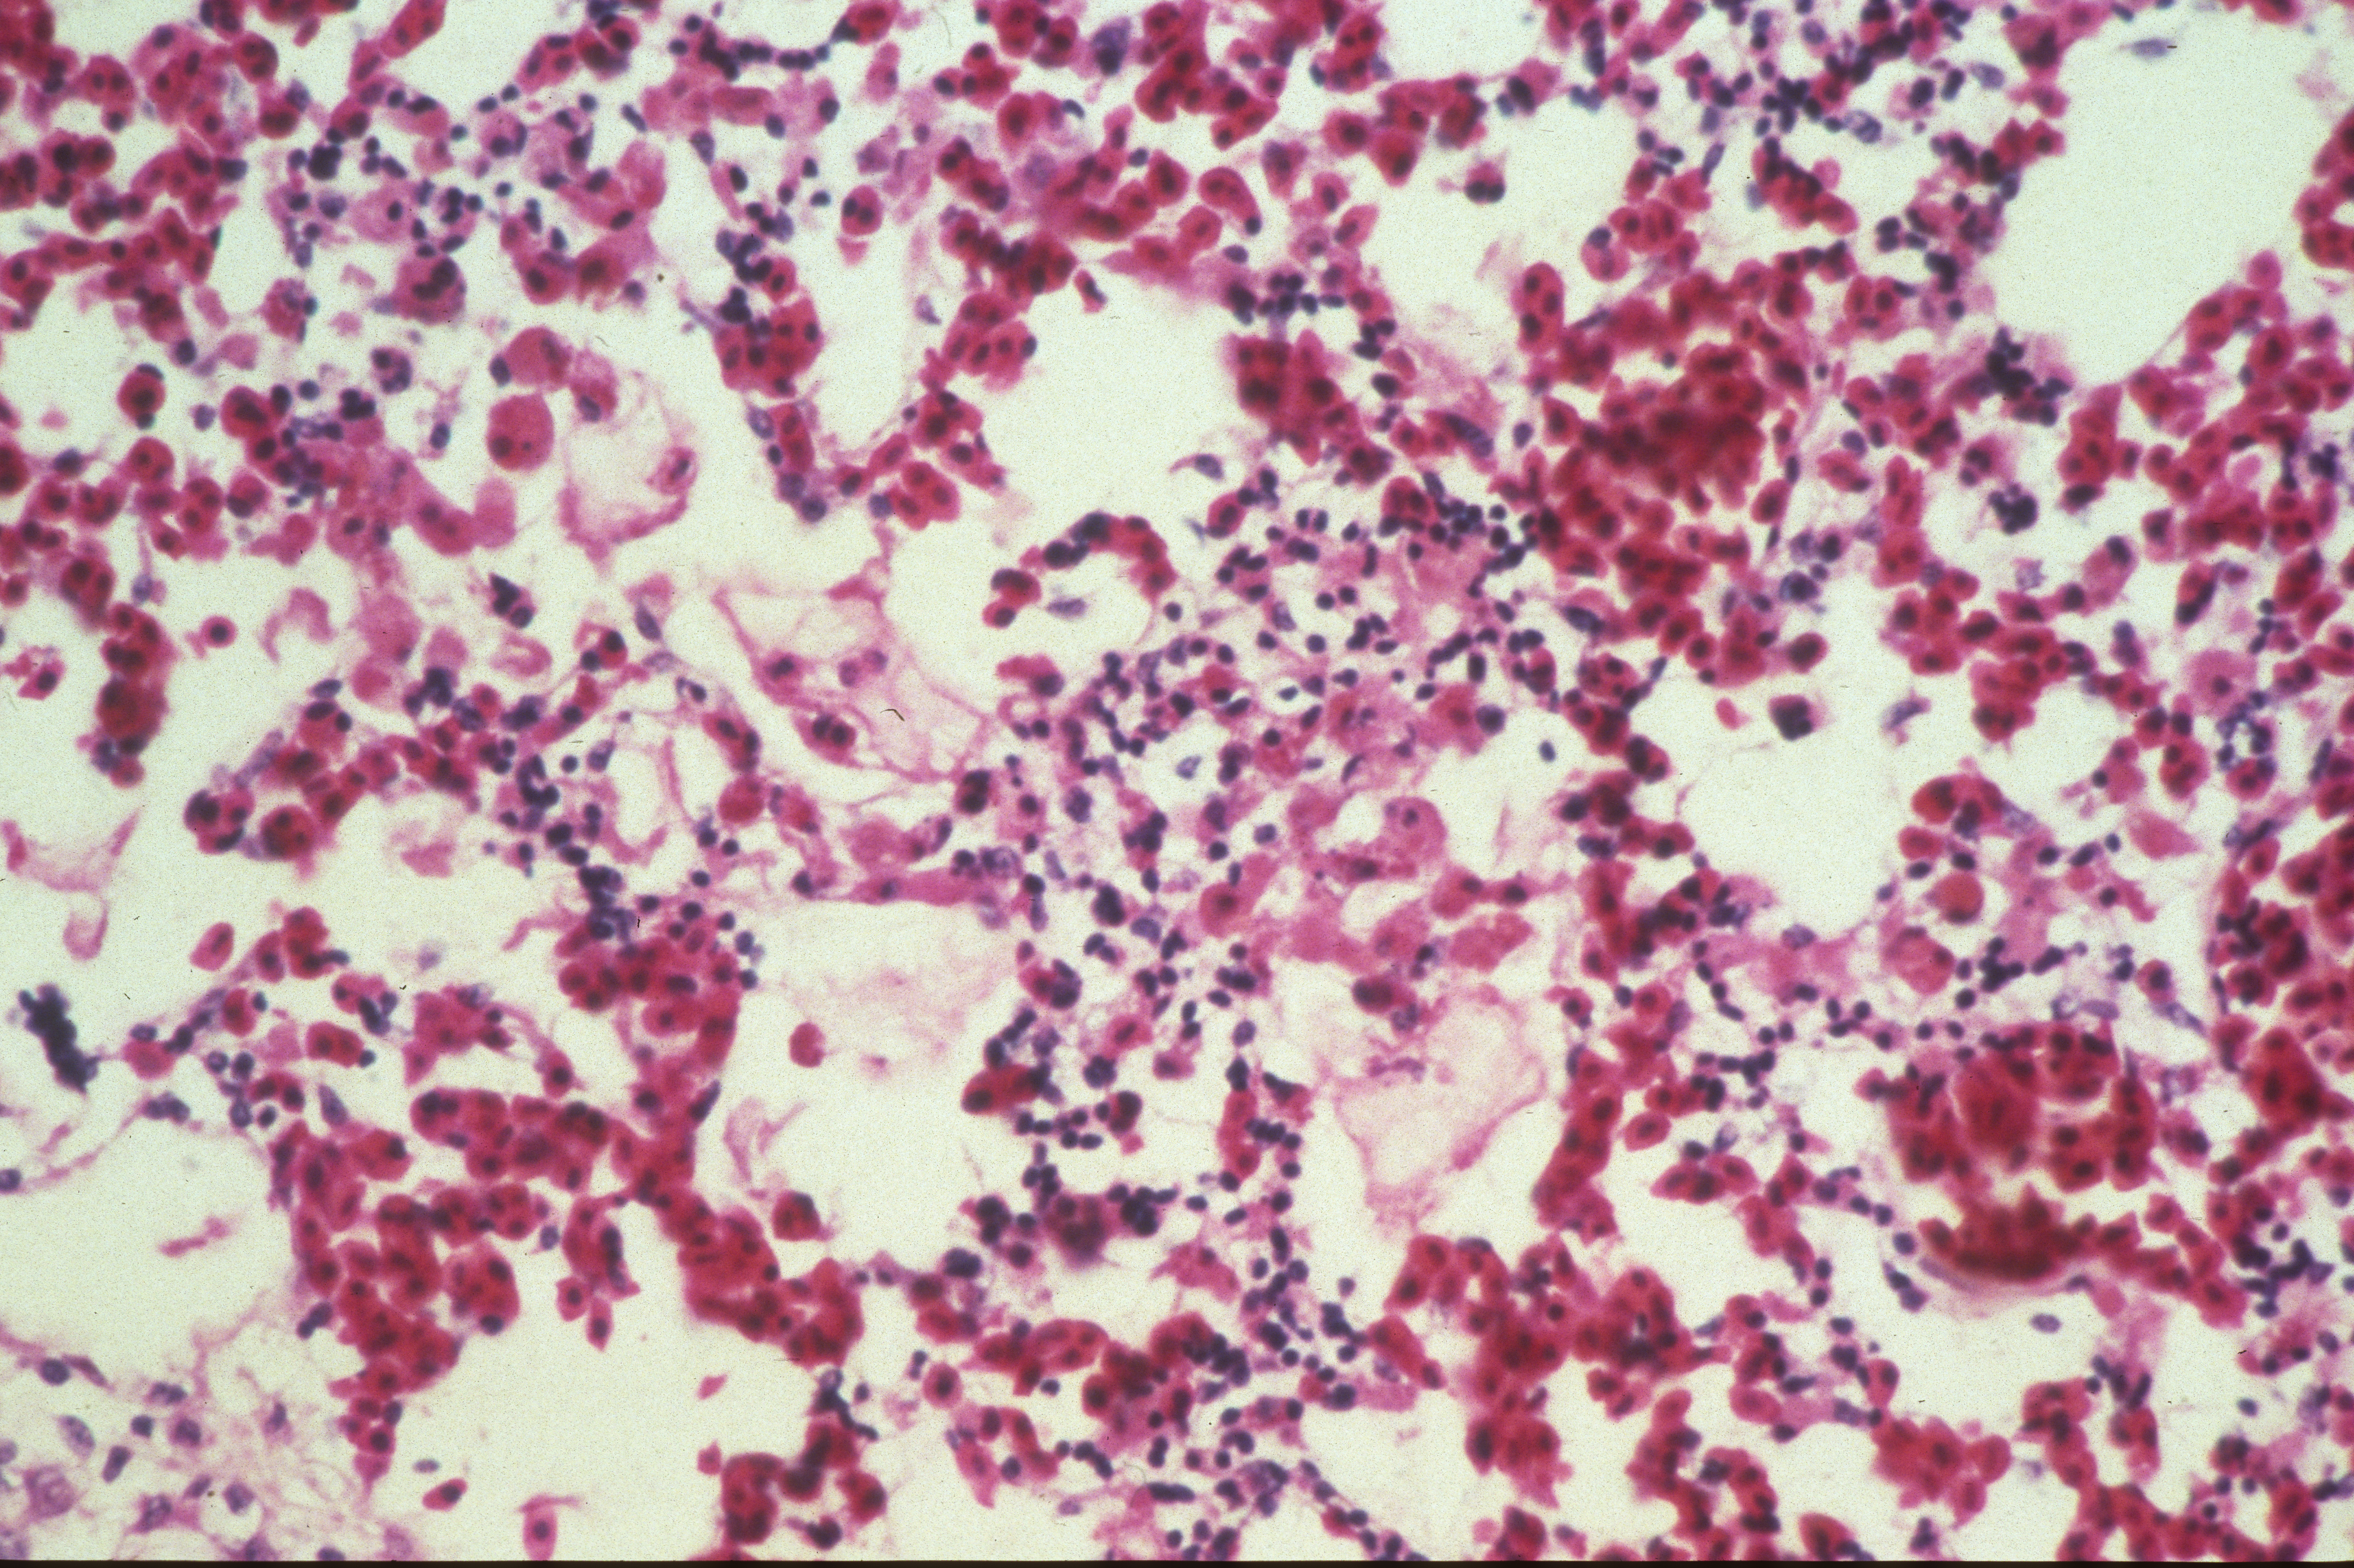

Marble spleen disease of ring-necked pheasants (slide study set no. 17) Item Info

Marble spleen disease of ring-necked pheasants (slide study set no. 17)

Slide study set #17, marble spleen disease of ring-necked pheasants, 2 sets (includes 40 color slides), undated